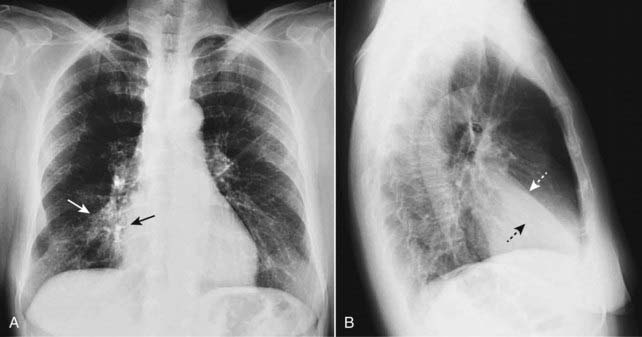

Figure 5-1 Right middle lobe atelectasis.

Frontal (A) and lateral (B) views of the chest show an area of increased density (solid white arrow), which is silhouetting the normal right heart border (solid black arrow) indicating its anterior location in the right middle lobe. On the lateral view (B), the minor fissure is displaced downward (dotted white arrow) and the major fissure is displaced slightly upward (dotted black arrow). Note the anterior location of the middle lobe.